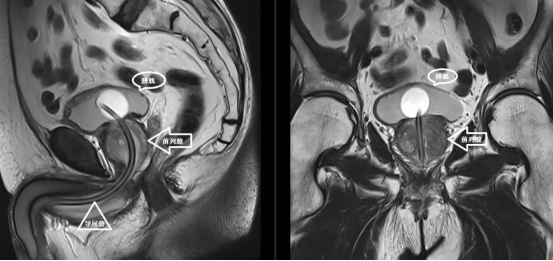

第三、要进行前列腺磁共振成像,通过核磁共振影像看看前列腺包膜、两侧精囊以及周围组织有无侵犯、破坏。

前列腺磁共振成像